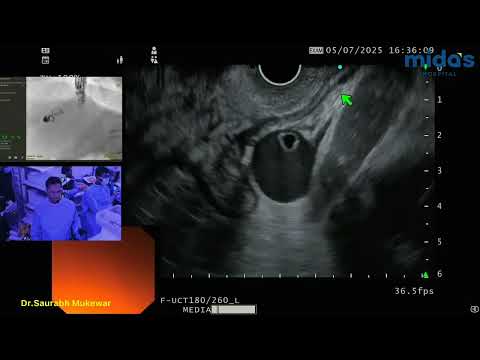

Live EUS-Guided Liver Biopsy (unedited) performed by Dr. Saurabh Mukewar